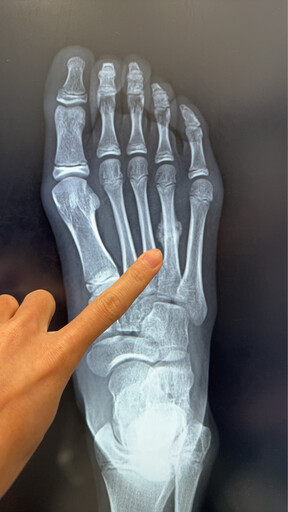

11歲女學童右側腳掌「蹠骨應力性骨折」,且已出現癒合跡象。

近日,陳建宏骨科診所接獲一名11歲女學童就醫個案,該學童因暑期密集參加田徑與球類訓練,右側腳掌疼痛兩周未緩,檢查後確診為「蹠骨應力性骨折」,且已出現癒合跡象。

陳建宏醫師說明,蹠骨位於腳掌前端,承受人體走路、跑跳時的主要壓力。當骨頭長期反覆承受過大的應力,而缺乏足夠休息與修復時間時,便可能出現顯微的骨折,這就是所謂的「應力性骨折」。